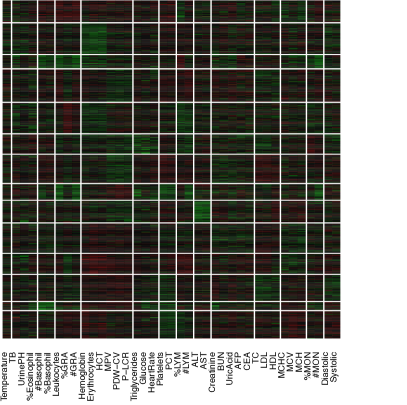

The data contain blood test results measured on 39 testing items which are listed in Table 1. Figure 1(a) shows the empirical correlation structure of the testing items as a heatmap with green, black, and red colors indicating positive, negligible and negative correlations. With appropriate ordering of the test items, one can see some patterns on the upper-left corner of the heatmap. However, the patterns seem vague and have no clear interpretation. The heatmap of the standardized data is shown in Figure 1 with green, black and red colors indicating values above, near and below the average. Next we cluster the data using a K-means algorithm with (the number of latent diseases identified in later model-based inference), applied to both, rows and columns of the data matrix. The clusters find some interesting structures. For example, indexing the submatrices in the heatmap by row and column blocks, the values in block (9,9) tend to be above the average, whereas the values in the block (1,4) tend to be below the average. However, there are at least two difficulties in interpreting the clusters as latent diseases. Firstly, there is no absolute relationship between the normal range of a testing item and its population average. A deviation from the average does not necessarily indicate an abnormality. Likewise, average values of testing items, especially those related to common diseases such as hypertension, are not necessarily within the normal range. For instance, the mean and the median of systolic blood pressure in our dataset are 147 mm Hg and 145 mm Hg, both of which are beyond the threshold 140 mm Hg for hypertension (the high blood pressure values might be related to the elderly patient population). Secondly, the exploratory analysis with K-means does not explicitly model patient-disease relationships and symptom-disease relationships. For example, one may be tempted to interpret each column block as a latent disease. As a consequence, each testing item has to be associated with exactly one disease and the patient-disease relationship is unclear. If instead, we define a latent disease by the row blocks, then each patient has to have exactly one disease and the symptom-disease relationship is ambiguous.

We can slightly improve interpretability by incorporating prior information. Specifically, each testing item comes with a reference range which we use to define symptoms: a symptom is an item beyond the reference range. In essence, we convert the original data matrix into a ternary matrix which is shown in Figure 1. The first difficulty is resolved but the second difficulty remains. For instance, the 6th column seems to suggest a disease with elevated total cholesterol and low density lipoproteins, which is also found in our later analysis with the proposed DFA. However, just as in Figure 1, it is hard to judge which blocks meaningfully represent latent disease since patient-disease relationships and symptom-disease relationships are not explicitly modeled. Besides the requirement of specifying the number of clusters, K-means is unsuitable for the task that we are pursuing in this paper.

Alternatively, instead of discretization, we can scale and center test items at the midpoint of each reference range. We show the heatmap in Figure 1 where the rows and the columns are arranged in the same way as in Figure 1. However, just as previous cases, the same limitation of interpretability still applies.